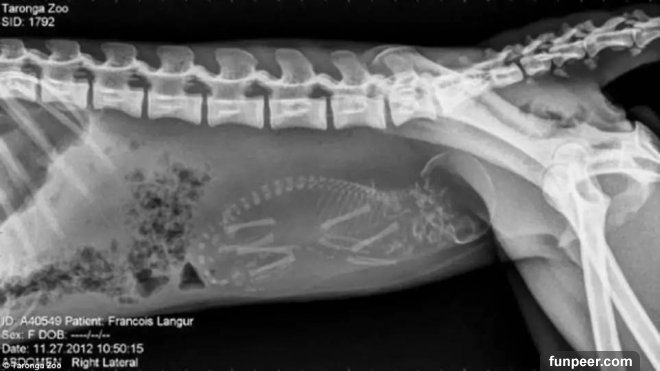

豚鼠的整個身體似乎都擠滿了孩子

某種卵胎生的蛇,因此不再顯示為蛋